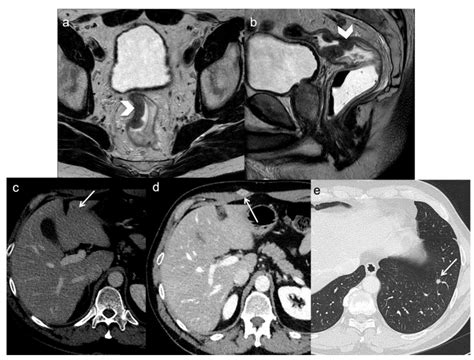

Imaging (MRI/CT) Assesses the extent and spread of the disease.